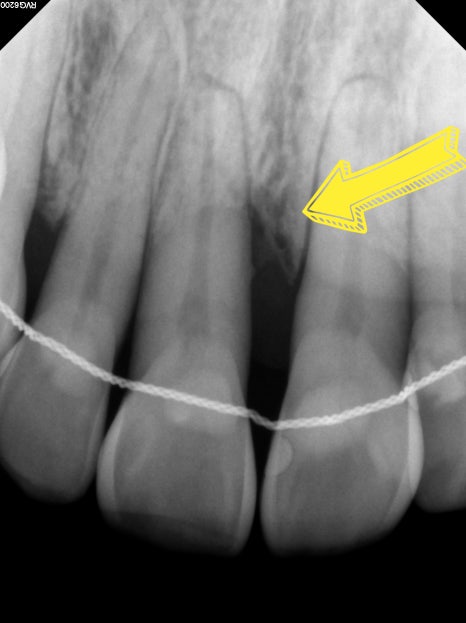

CASE 2. "앞니 잇몸이 내려가서 보기 싫어요"

앞니 부위의 잇몸뼈 소실이

비교적 크게 진행되어

치아 뿌리가 많이 노출된 상태로

기능적인 불편감 보다는

심미적인 부분에 고민이 되셔서 내원하셨습니다

다행히 치아의 흔들림은 크지 않은 상태였으며

담당 원장님 진단 하에

엠도게인 치주 재생 치료를 진행하였습니다

치료 후 약 1개월 경과 시

잇몸뼈 재생이 진행되는 양상을

관찰할 수 있었으며,

자연치아 보존 가능성을

함께 지켜볼 수 있었던 사례입니다